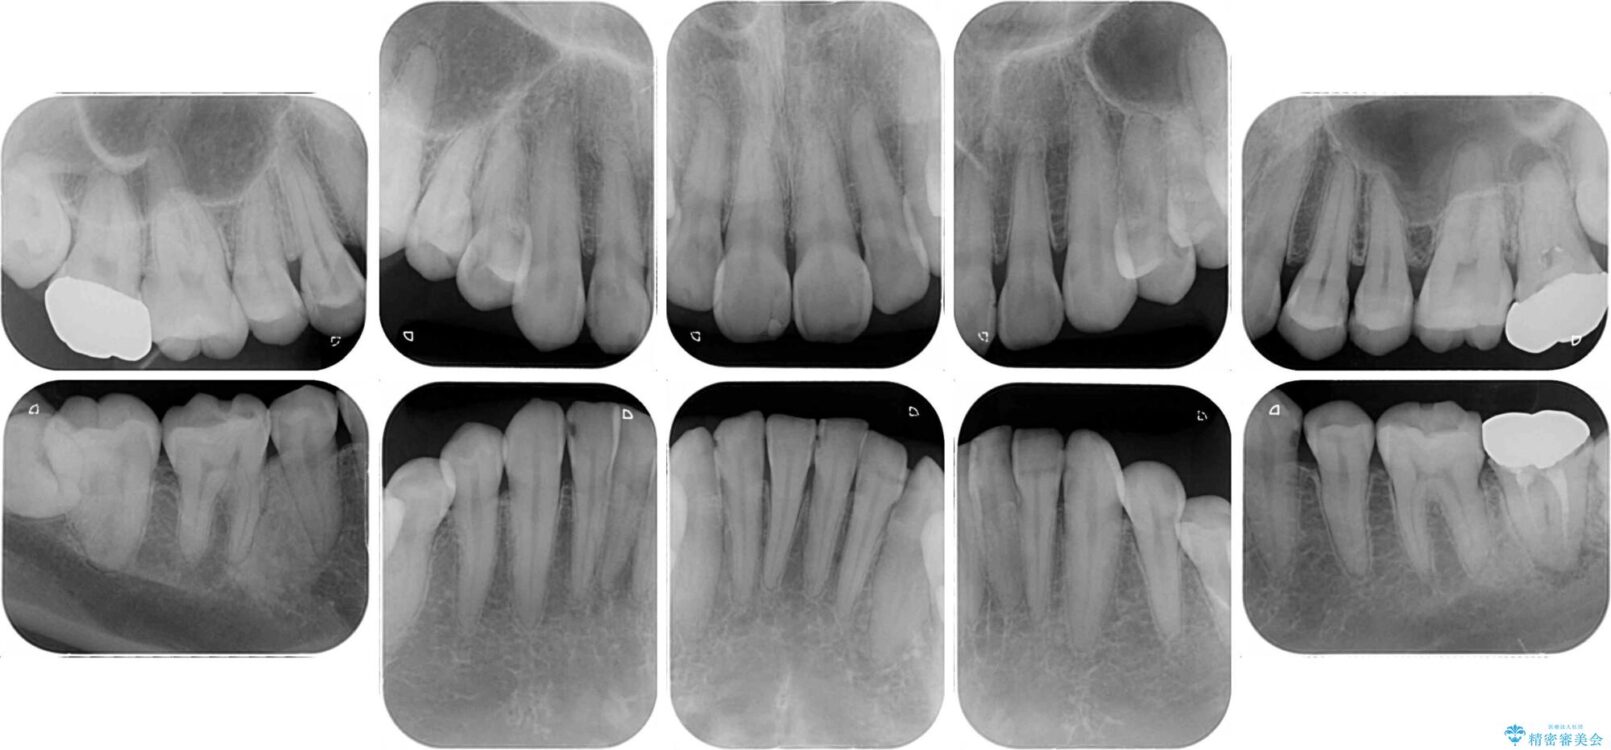

上下前歯や奥歯の虫歯治療を希望して来院された患者様です。

全顎的にむし歯が多く、根管治療の必要な奥歯や、審美的に気になっている前歯を中心にオールセラミッククラウンにて補綴治療を行うこととしました。

治療前

• むし歯だらけの前歯をオールセラミッククラウンできれいに 治療前画像